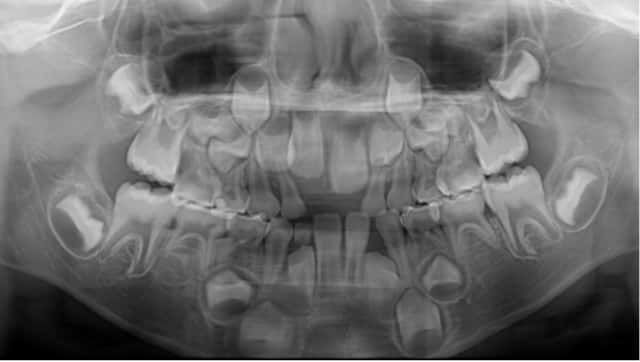

- レントゲン写真

![レントゲン写真]()